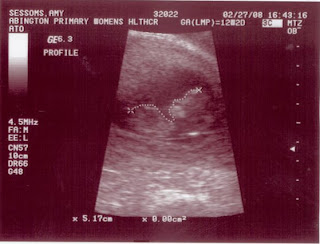

We had our fist ultra sound last Wednesday. My mom and I went and we both cried!! he he. I will be going for another ultrasound this wednesday. They saw a cyst on my right ovary so they want to get a better look at it, and see what we need to do or if it is nothing to worry about right now. My next monthly appointment with the doctor is on the 19th.